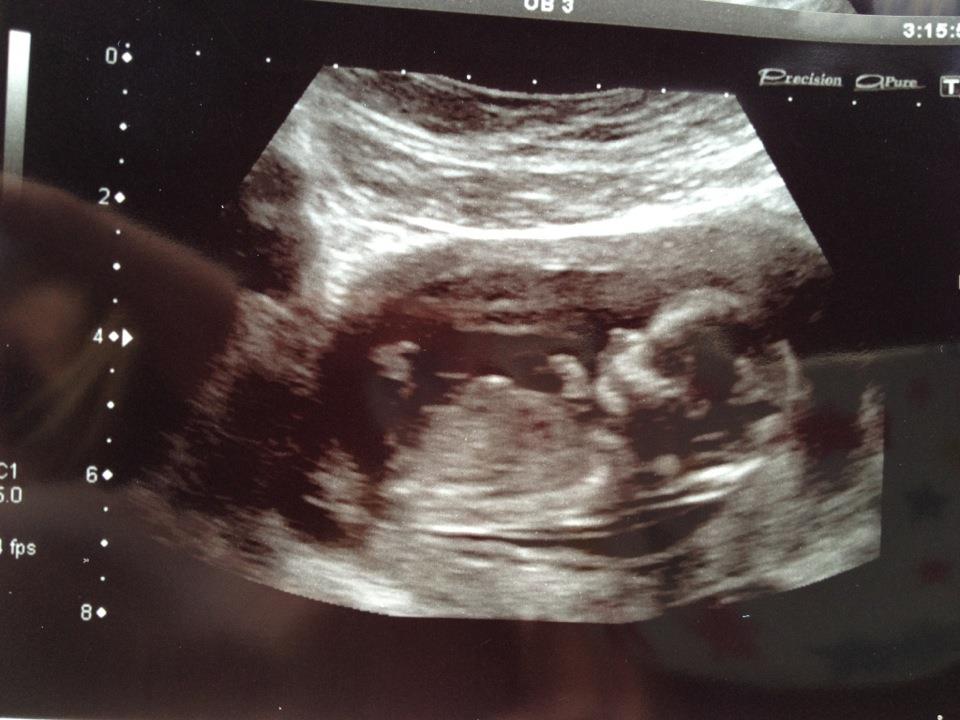

Attachment 3930Attachment 3930Attachment 3929my 1st baby and 9 weeks to go!!!! i didnt find out ! now wishing i had!!:) so any guesses xxxxxx

If what I think is the nub, then girl :)

I think Boy from skull...

The first 2 look girl but the third looks boy and skull looks boy... 50/50! You're so close to finding out your suprise!!

Boy by skull. GL

i'd say boy - i think i see a lil nubber in 2 of the pics. GL!

I guess boy